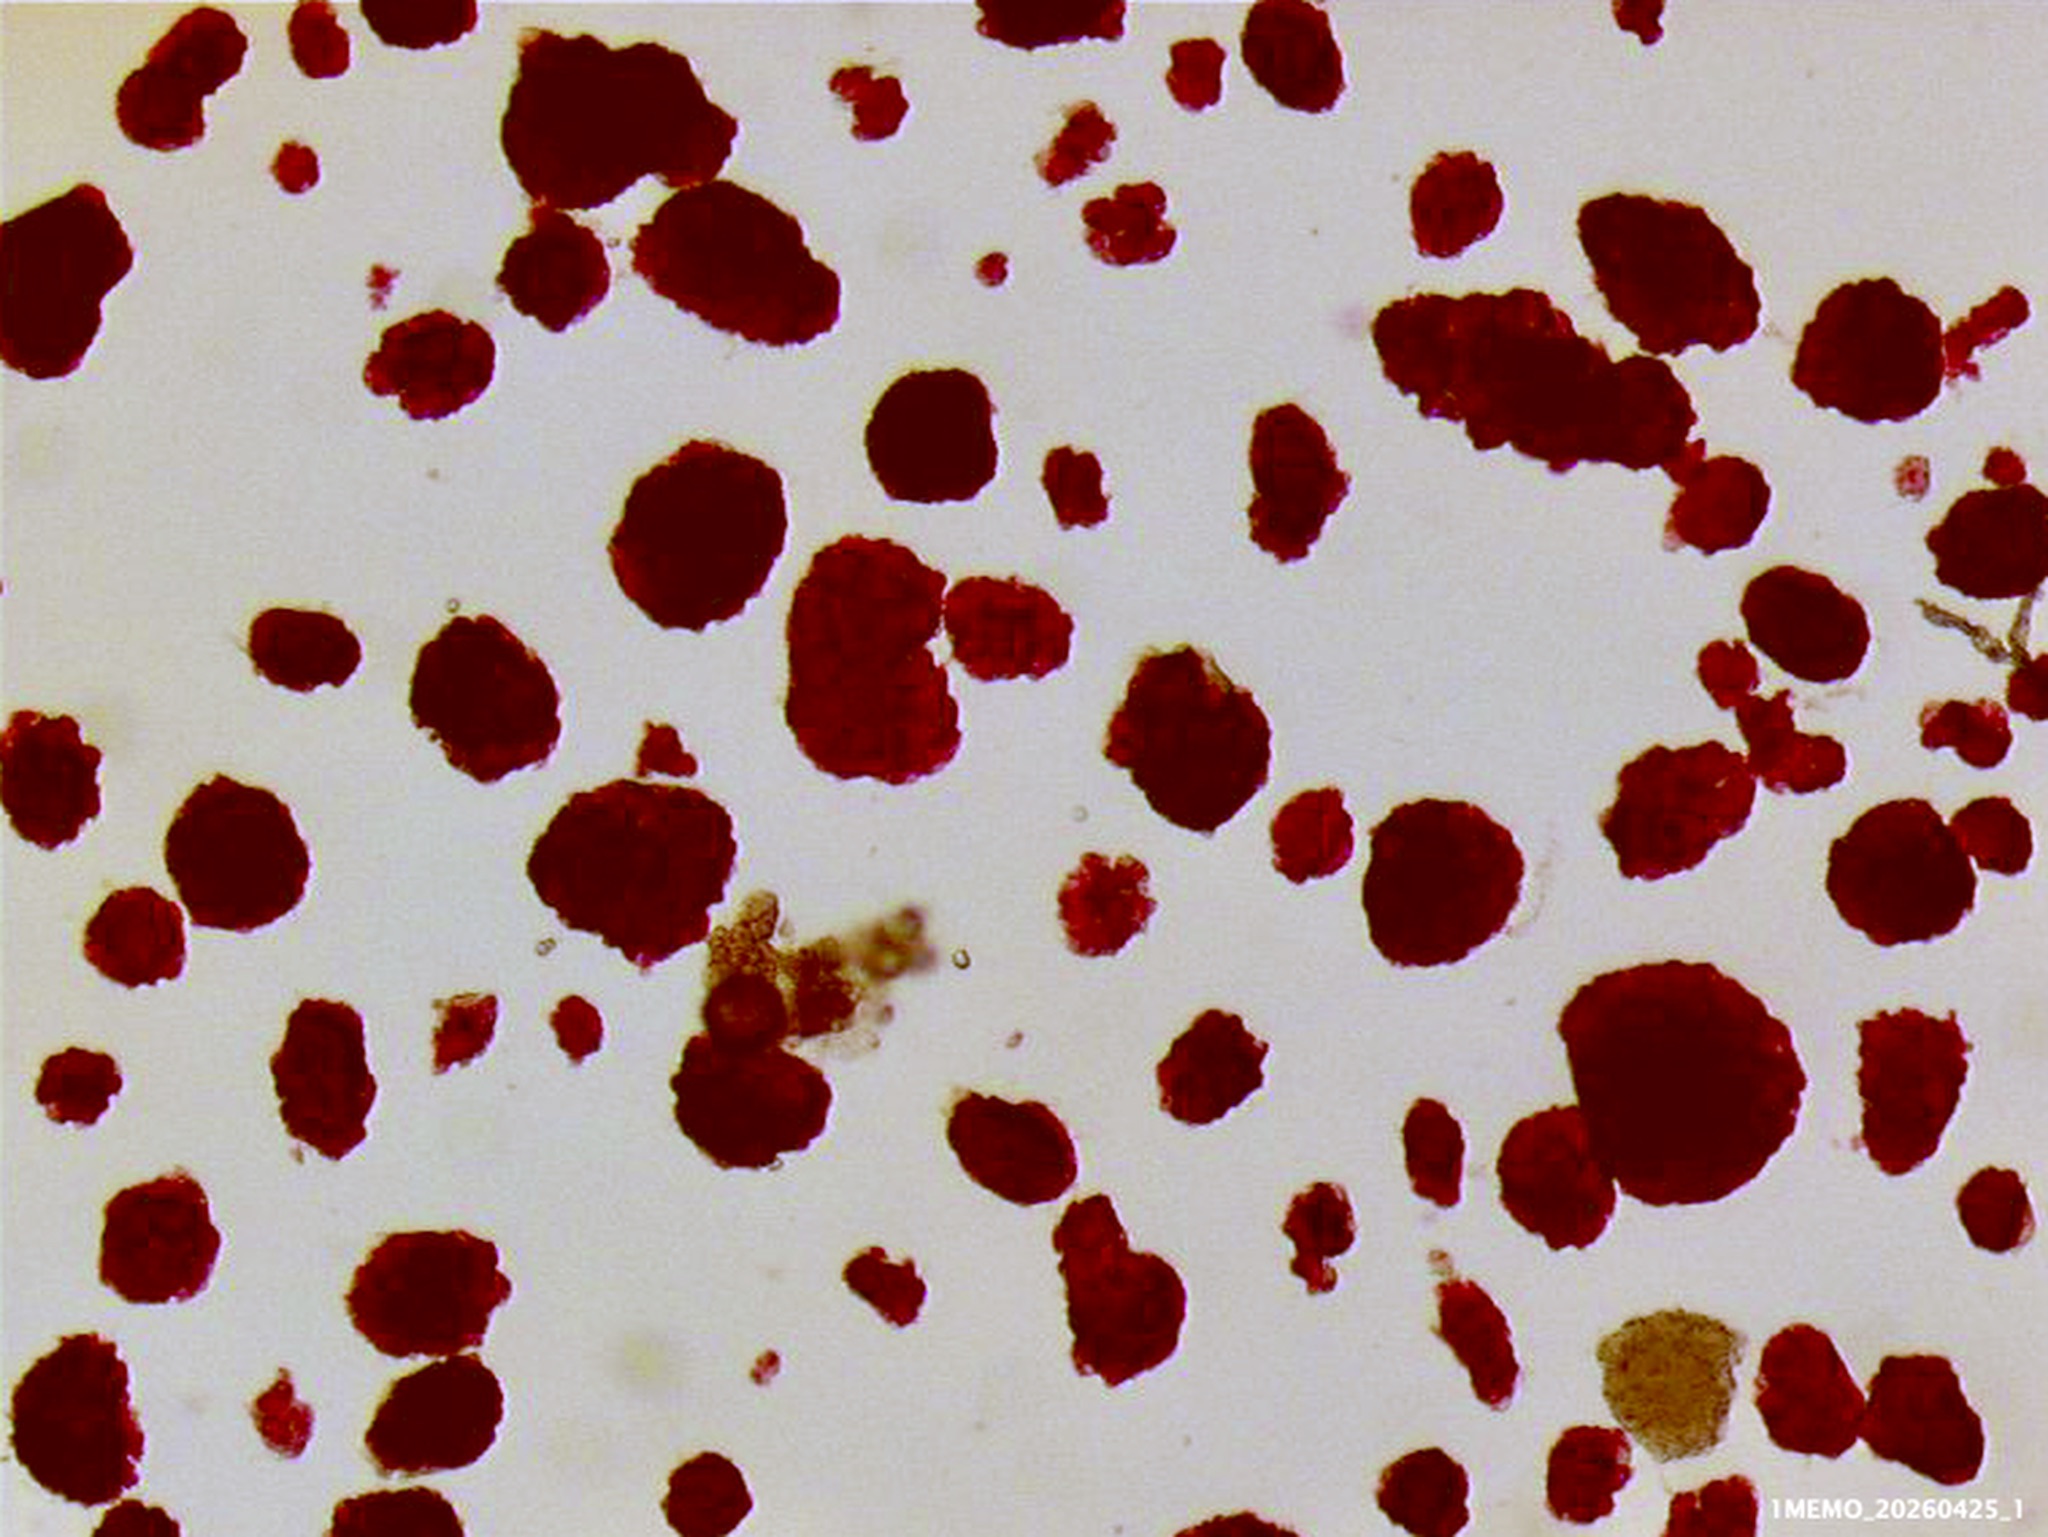

I photographed the isolated cynomolgus islets both before culture (stained red with dithizone), and after one day culture (not stained, in the petri dishes used for culture).

Survival of 98% of the islets after staying one day in suspension in a culture solution at 37°C demonstrated the excellent viability of these cynomolgus islets.

The viability was confirmed by staining these cultured islets with a mixture of two fluorescent dyes — acridine orange and propidium iodide (AO/PI). Fluorescence microscopy shows the live (green) cells , and few dead (red/yellow) cells in these islets.